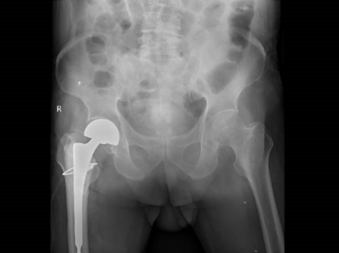

郑伯接受的是人工髋关节置换手术,刘兴漠与团队默契配合,将新的人工关节置于骨骼之中,手法娴熟,精准落位,仅用一小时就完成手术。术后郑伯直接返回普通病房,当天下午就能在病床上自主活动。

更令人惊喜的是,在叶伟护士长带领的护理团队精心护理下,随着早期下床活动,原本反复发作的哮喘症状明显改善,郑伯术后第三天已能扶助行器行走。

随后,郑伯在医师指导下进行步态康复训练,约一周就顺利返家与老伴团聚。